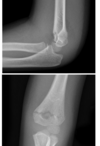

5

How well did you know this?

1

Not at all